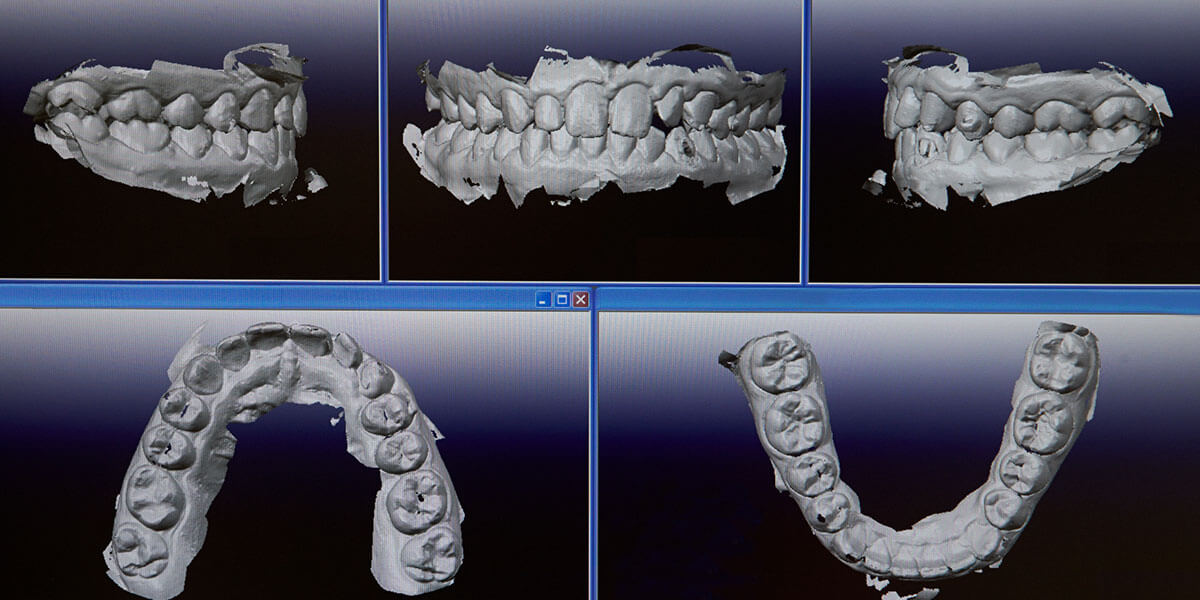

Digital Intraoral Scanner

Impressions have traditionally involved making a mold of your teeth using trays filled with a soft, messy, and often bad-tasting material that would harden around the patients’ teeth and gums, creating a precise model that is then used by the doctors and the lab to plan treatment and create final restorations.

The digital intraoral scanner provides a new, comfortable, and precise way for our office to take digital impressions of patients’ teeth. Taking accurate impressions of a patient’s teeth is a highly important part of a large number of dental and orthodontic procedures.